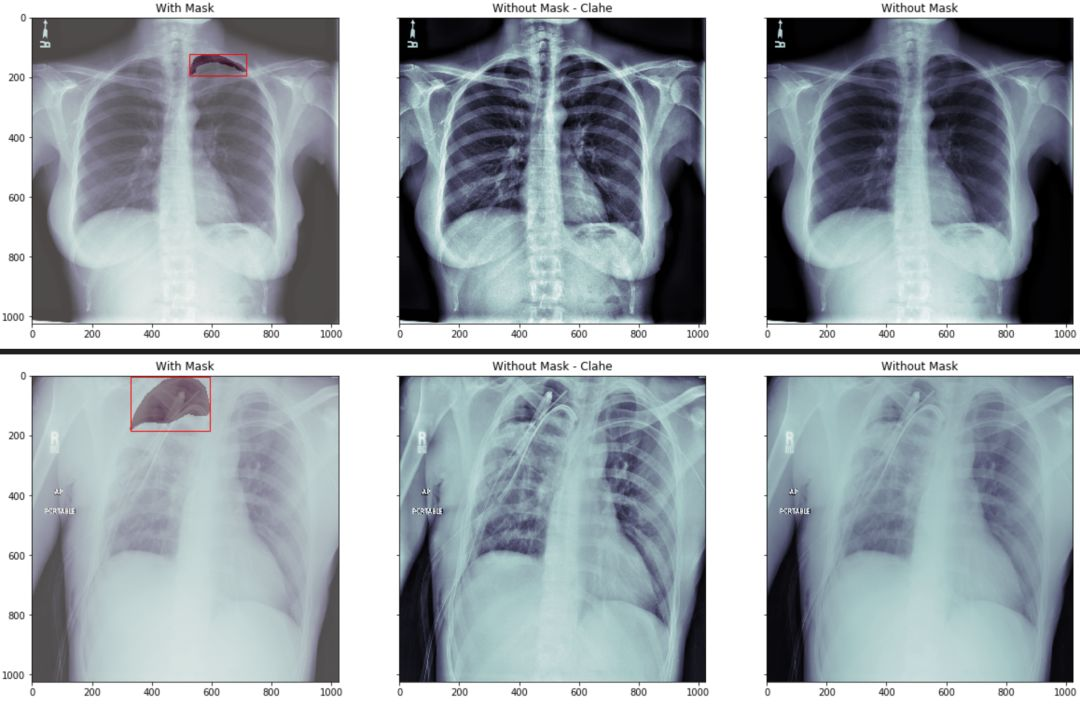

我们在看下 mask 图像在相对应的病例中的位置:

我们分三组来显示

第一组我们将原始胸片图像中用红色的框框出 mask 的最小包围盒. 然后将mask 数据部分用不同的颜色区分

第二组我们将原始图像做直方图均衡化处理,让胸片对比度更加清晰。

第三组我们直接显示原始图像

通过观察我们看到,如果没有一定的专业知识,根本无法区分跟看出气胸的具体位置。

结果如图示: